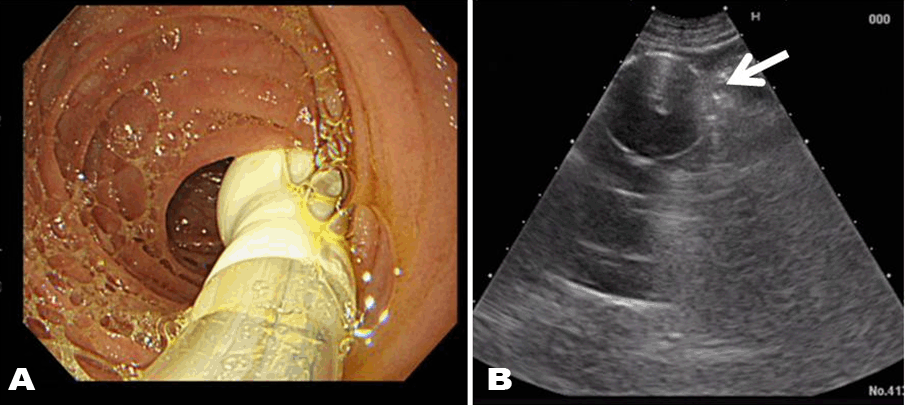

A 56-year-old man presented with alcoholic encephalopathy and alcoholic liver cirrhosis in April 2014. He was 165 cm height and 41 kg weight. He had a past history of total gastrectomy for gastric cancer when he was 51-year-old. Because he had dysphagia, we performed USPEJ to him in May 28, 2014. Ileus tube was inserted into the jejunum and its balloon was expanded with 20 ml water under observation by endoscopy (Figure 1A). Abdominal ultrasonography was performed to find the balloon of ileus tube with a puncture probe (Figure 1B). When we found the balloon, we punctured the jejunum just beside the balloon by using a regular puncture needle of PEG kit after local anesthesia. The jejunal tube was placed as a jejunostomy tube with an ordinal pull- through method of PEG. Four days after USPEJ jejunal nutrition was started safely.

Figure 1: (A) A balloon of ileus tube is placed in jejunum and expanded after with watching by endoscopy; (B) A expanded balloon of ileus tube is easy to find by ultrasonography (arrow)